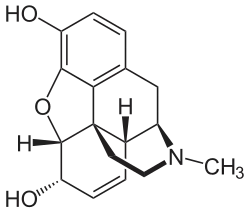

Die Strukturformel von Morphin

Die Strukturformel von Morphin -

Das Diffusionsvermögen eines Moleküls durch die Endothelien der Blut-Hirn-Schranke wird vor allem durch seine Fettlöslichkeit (Lipophilie) und Größe bestimmt. Durch eine Modifizierung des Moleküls mit lipophilen Gruppen kann deshalb eine verbesserte Gehirngängigkeit erreicht werden.[33] Ein klassisches Beispiel hierfür ist die Di-Acetylierung des Naturstoffes Morphin zu Diacetylmorphin (Heroin). Heroin (log P=1,12) zeigt gegenüber Morphin (log P=0,2) eine über 25fach höhere Aufnahme im Gehirn (siehe dazu: Tabelle 1).[34] Entsprechende Ergebnisse werden beim Brain-Uptake-Index (BUI) für radioaktiv markiertes Morphin, Codein und Heroin erhalten, das in die Halsschlagader injiziert wird. Für Morphin liegt der BUI unterhalb der Nachweisgrenze, bei Codein bei 24 % und für Heroin bei 68 %.[35]